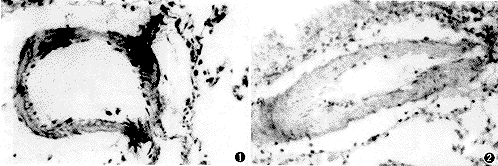

HPH大鼠肺小动脉平滑肌细胞上HERG基因表达明显低于正常大鼠,见图1,2。

图1 正常大鼠肺小动脉平滑肌HERG基因表达明显 原位杂交×400

图2 低氧性肺动脉高压大鼠肺小动脉平滑肌增生肥厚,HERG基因表达明显减少 原位杂交×400